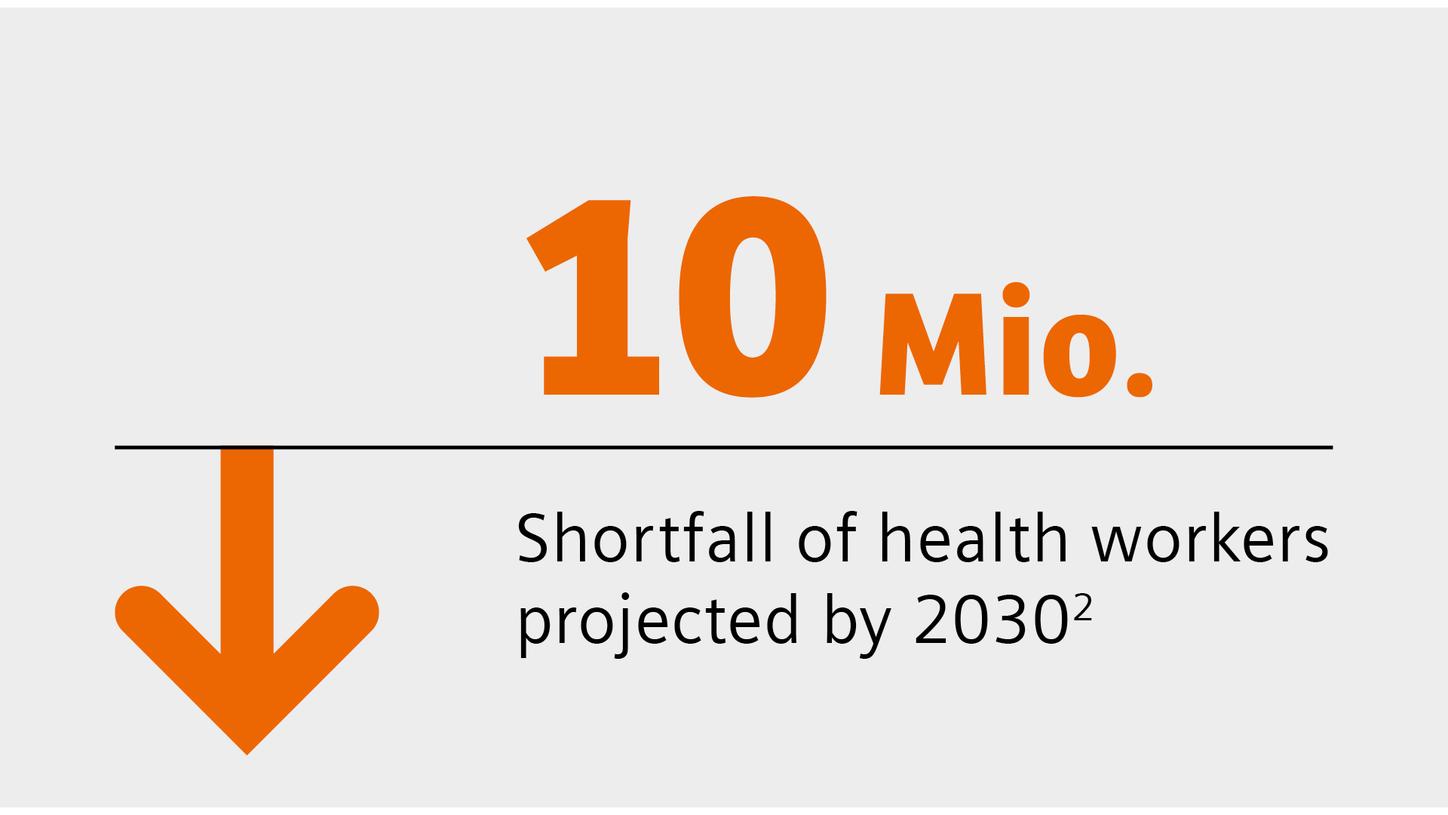

We are empowering decision making for technologists, radiologists, and clinicians along the whole imaging value chain and making it even smarter – allowing healthcare professionals to make the right decision at the right time within the patient pathway. Our AI-powered solutions are not just tools but essential allies in the modern medical imaging landscape, designed to increase productivity, improve clinical precision, and be integrated seamlessly.